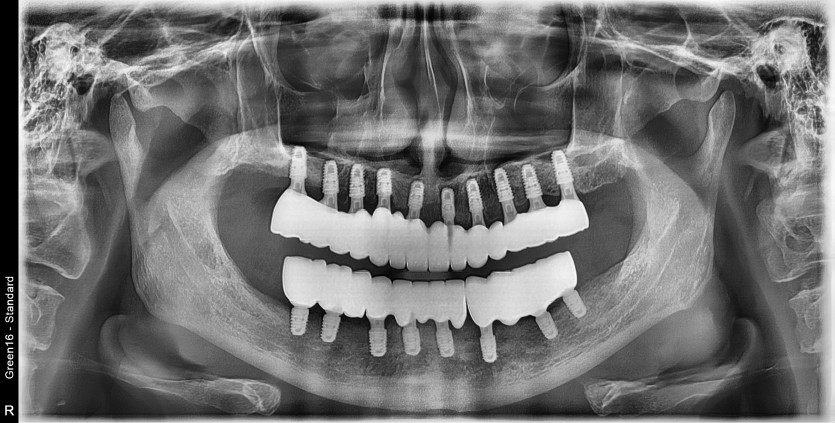

만 58세 전체 임플란트 증례

전체 임플란트 증례입니다.

18개의 임플란트로 완성하였습니다.